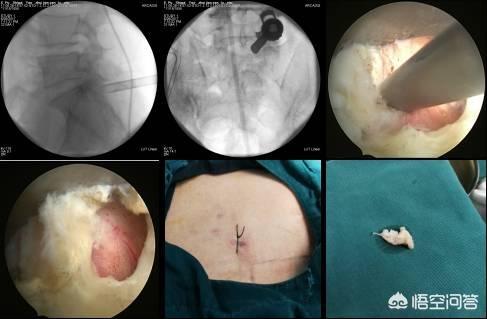

腰椎椎間板ヘルニアの手術は、現在、低侵襲手術と開腹手術の2種類があります。低侵襲手術には、高周波、プラズマ、椎間孔内視鏡などがあります。前二種類の手術は、より外傷が少なく、回復が早い疼痛科で行われますが、椎間板ヘルニアの小さい症例に限られ、過去の経験によると、急性発症時の鎮痛効果はまだ非常に良好です。

高周波熱凝固療法は、直径0.7mmの高周波針を使用し、C-armまたはCTガイダンスの下で穿刺し、病変椎間板に正確に到達して熱凝固のスイッチを入れる。熱放射に頼って髄核ヘルニアを小さくし、神経根の圧迫を和らげる。プラズマ手術と高周波熱凝固療法の違いは、ヘルニア髄核組織を直接蒸発させることです。

椎間板ヘルニアが大きい場合、椎間孔径手術の効果が良い。 椎間孔径手術の切開は小さく、通常7mm程度で、傍椎骨筋や靭帯を破壊せず、出血が少なく、脊椎の安定性に影響がなく、術後は神経圧迫が除去されるため、痛みの症状が早く緩和される。開腹手術は腰椎椎間板ヘルニアに腰椎変性症、骨棘、脊柱管狭窄症、神経根管狭窄症、靭帯石灰化などを伴う患者や、明らかに腰椎が不安定な患者が対象です。